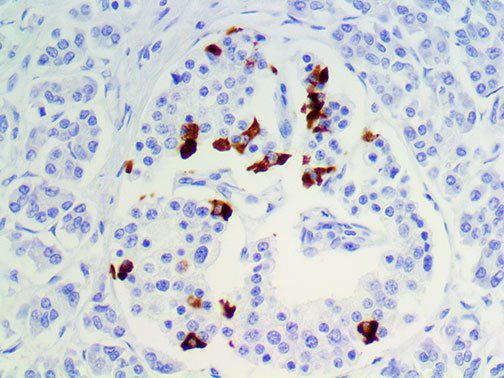

It is the ICU physician who is most likely to witness one of the deadliest manifestations of the abnormal immunological response, the cytokine storm syndrome (CSS). This response is also referred to by some as the cytokine release syndrome (CRS). CSS is characterized by continuous activation and expansion of macrophage and lymphocyte populations, which secrete large amounts of cytokines, causing the cytokine storm. This massive cytokine release is akin to hemophagocytic lymphohistiocytosis (HLH) disease, a syndrome characterized by initial unchecked and persistent activation of cytotoxic T lymphocytes and NK cells.

Clinical and laboratory manifestations of HLH include fever, enlarged liver and/or spleen, neurologic dysfunction, coagulopathy, liver dysfunction, cytopenias (i.e., low levels of erythrocytes, leukocytes, and/or platelets), hypertriglyceridemia, hyperferritinemia, hemophagocytosis, and eventually diminished NK cell activity as the immune system becomes progressively paralyzed. HLH can be familial (primary HLH) or secondary to another disease process (sHLH), such as rheumatic disease, in which it is referred to as macrophage activation syndrome (MAS, characterized by elevated ferritin).